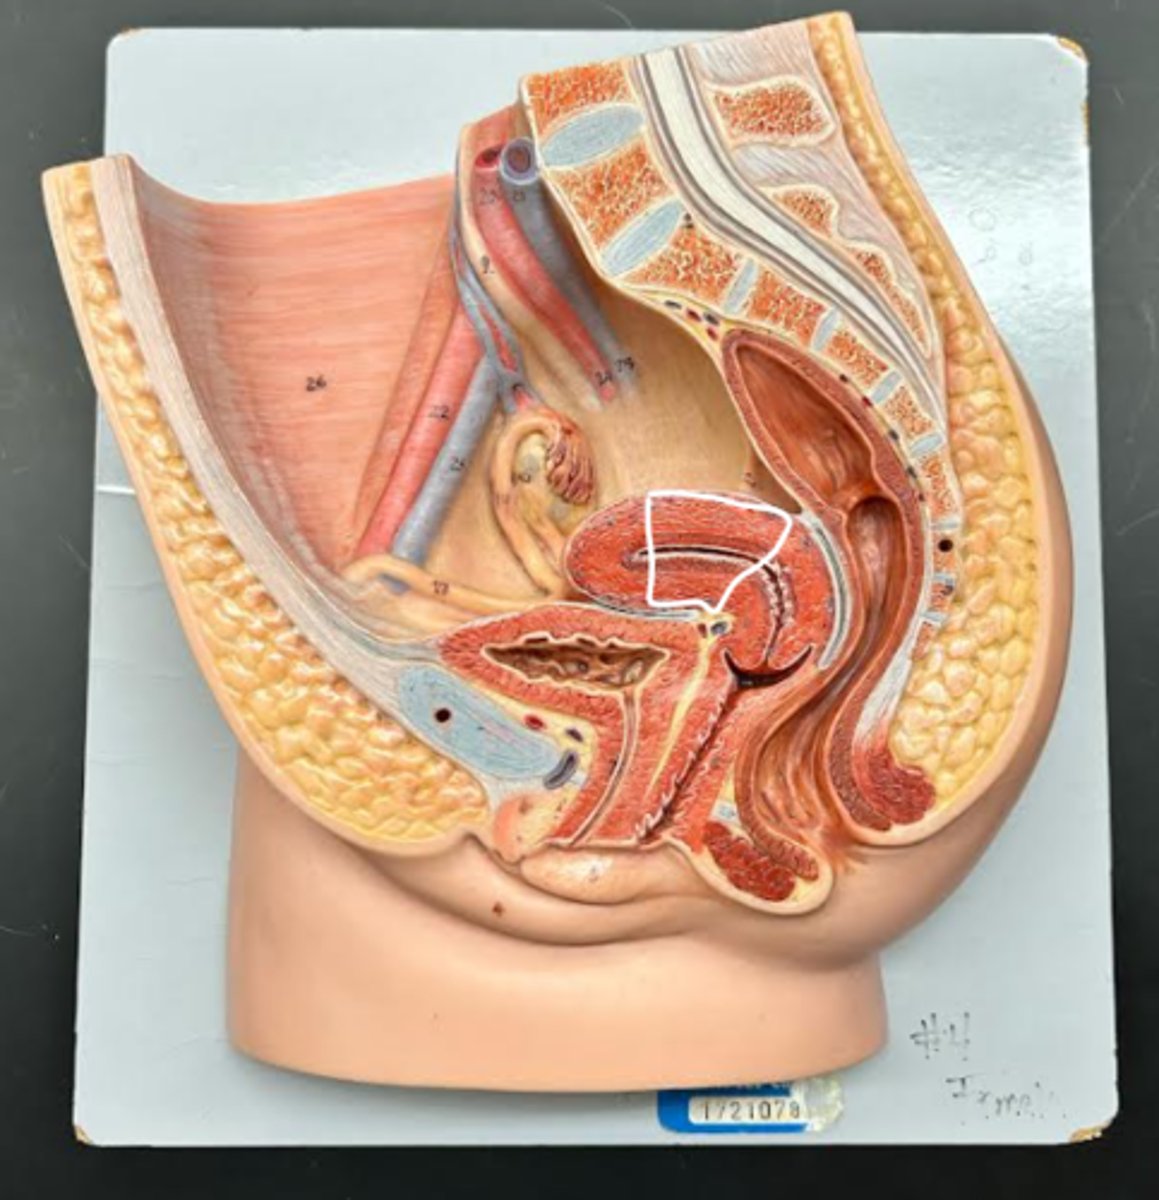

Chapter 29 Anat Phys: Female Reproductive System

Vagina

Vaginal orifice

Hymen

Vaginal fornix

Ovary

Fallopian tube

Fimbriae

Infundibulum

Ampulla

Isthmus

Uterus

Perimetrium

Myometrium

Endometrium

Fundus

Body of uterus

Cervix

Internal os

Cervical canal

External os

Labia majora

Labia minora

Prepuce

Vestibule

Clitoris

External urethral orifice